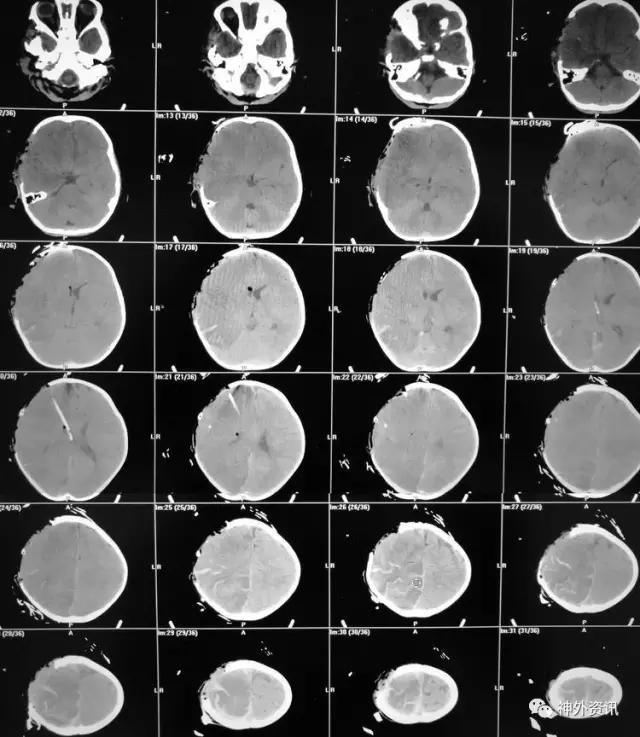

术后移动CT结果示中线移位较术前减轻,顶枕部蛛网膜下腔出血:

2017.2.1:术后2天复查颅脑CT,结果示中线居中,右侧半球低密度并SAH,左侧半球未见明显异常,左侧脑沟可见显示,双肺少量炎症,不能放松警惕,继续同前治疗。

2017.2.4:术后5天复查颅脑CT,结果示中线居中,左侧半球及环池显示清晰,右侧半球脑沟显示欠清晰,脑组织低密度较前有所好转,继续同前治疗。已加用预消化肠内营养液及促进胃肠动力药物。

2017.2.6:术后7天,复查颅脑CT示情况较前进一步好转,逐步撤掉冰毯,缓慢自然复温。

2017.2.8:术后9天,复查颅脑及胸部CT,结果显示双侧脑沟脑回及环池显示清晰。颅压控制,拔除引流管探头,头部敷料稍加压包扎,此时已更替力月西为丙泊酚,停用呼吸机。